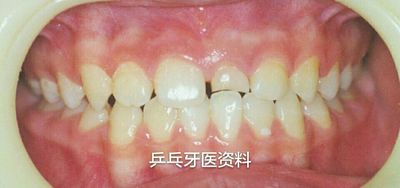

前牙间隙过大提示可能有多生牙